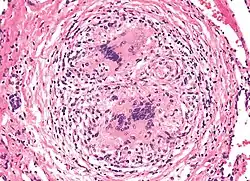

Beryloza (przewlekła choroba berylowa, berylioza, ang. berylliosis, chronic beryllium disorder, CBD) – przewlekła choroba zawodowa wynikająca z zatrucia berylem, przede wszystkim spowodowana kontaktem z pyłem berylowym. Dotyczy uszkodzeń układu oddechowego, przede wszystkim płuc, ale mogą występować także obrażenia skóry. Klinicznie bardzo przypomina sarkoidozę.

Za wywołujące ostrą berylozę uważa się stężenie powyżej 100 μg/m³[1]. Wdychanie niskich stężeń powoduje berylozę w formie przewlekłej, np. przewlekłej choroby ziarniniakowej[a], objawiającą się upośledzeniem funkcji oddechowych (dusznościami, kaszlem), i innymi symptomami, w tym utratą wagi[1]. Ma ona charakter odpowiedzi alergicznej[2]. Uczulenie na beryl dotyczy około 16% populacji. Nadwrażliwość na beryl jest typu komórkowego; beryl indukuje proliferację limfocytów T CD4+, uwalnianie cytokin, rekrutację makrofagów i tworzenie ziarniniaków.